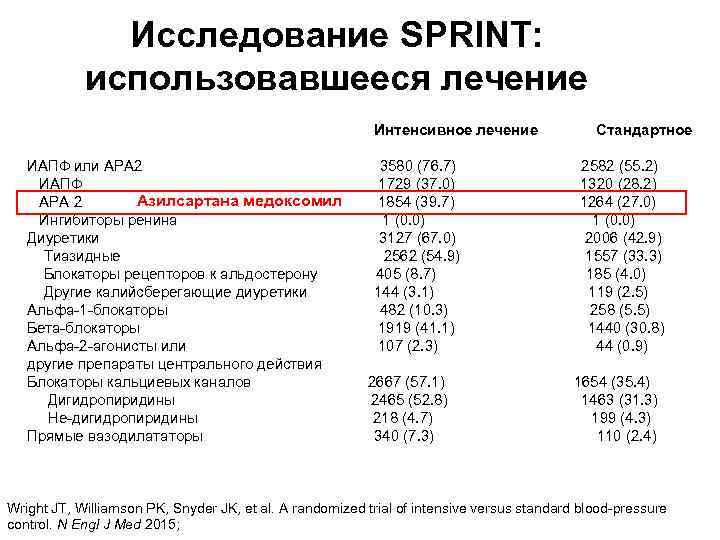

Исследование SPRINT: использовавшееся лечение Интенсивное лечение Стандартное ИАПФ или АРА 2 3580 (76. 7) 2582 (55. 2) ИАПФ 1729 (37. 0) 1320 (28. 2) Азилсартана медоксомил АРА 2 1854 (39. 7) 1264 (27. 0) Ингибиторы ренина 1 (0. 0) Диуретики 3127 (67. 0) 2006 (42. 9) Тиазидные 2562 (54. 9) 1557 (33. 3) Блокаторы рецепторов к альдостерону 405 (8. 7) 185 (4. 0) Другие калийсберегающие диуретики 144 (3. 1) 119 (2. 5) Альфа-1 -блокаторы 482 (10. 3) 258 (5. 5) Бета-блокаторы 1919 (41. 1) 1440 (30. 8) Альфа-2 -агонисты или 107 (2. 3) 44 (0. 9) другие препараты центрального действия Блокаторы кальциевых каналов 2667 (57. 1) 1654 (35. 4) Дигидропиридины 2465 (52. 8) 1463 (31. 3) Не-дигидропиридины 218 (4. 7) 199 (4. 3) Прямые вазодилататоры 340 (7. 3) 110 (2. 4) Wright JT, Williamson PK, Snyder JK, et al. A randomized trial of intensive versus standard blood-pressure control. N Engl J Med 2015;

Исследование SPRINT: использовавшееся лечение Интенсивное лечение Стандартное ИАПФ или АРА 2 3580 (76. 7) 2582 (55. 2) ИАПФ 1729 (37. 0) 1320 (28. 2) Азилсартана медоксомил АРА 2 1854 (39. 7) 1264 (27. 0) Ингибиторы ренина 1 (0. 0) Диуретики 3127 (67. 0) 2006 (42. 9) Тиазидные 2562 (54. 9) 1557 (33. 3) Блокаторы рецепторов к альдостерону 405 (8. 7) 185 (4. 0) Другие калийсберегающие диуретики 144 (3. 1) 119 (2. 5) Альфа-1 -блокаторы 482 (10. 3) 258 (5. 5) Бета-блокаторы 1919 (41. 1) 1440 (30. 8) Альфа-2 -агонисты или 107 (2. 3) 44 (0. 9) другие препараты центрального действия Блокаторы кальциевых каналов 2667 (57. 1) 1654 (35. 4) Дигидропиридины 2465 (52. 8) 1463 (31. 3) Не-дигидропиридины 218 (4. 7) 199 (4. 3) Прямые вазодилататоры 340 (7. 3) 110 (2. 4) Wright JT, Williamson PK, Snyder JK, et al. A randomized trial of intensive versus standard blood-pressure control. N Engl J Med 2015;